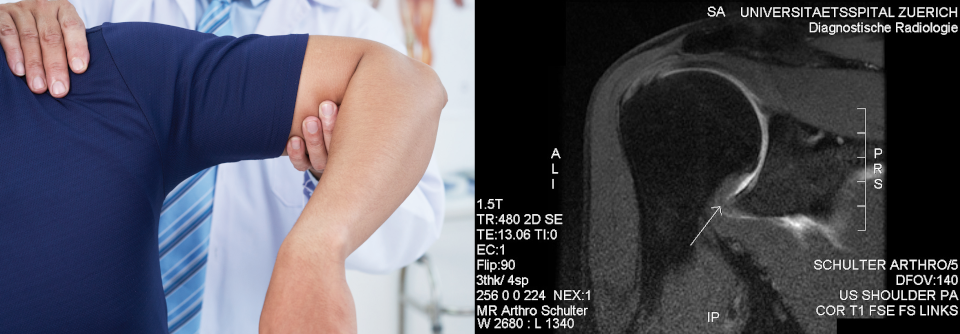

Zu den Risikofaktoren für einen Knochenbruch zählen Alter > 40 Jahre, erste Luxation und Hochenergietrauma (z.B. Sturz aus großer Höhe). Eine weitere Komplikation, die Ruptur der Rotatorenmanschette, lässt sich klinisch manchmal schwer diagnostizieren. Verdächtig sind persistierende Schmerzen und bleibende funktionelle Einschränkungen trotz Physio­therapie.

• über 40-Jährige mit anhaltenden Schmerzen und dauerhaft eingeschränkter Funktion (V.a. Ruptur

Nach einer erstmaligen Luxation sollte die Reposition in einer Unfallambulanz erfolgen. Bei Jüngeren (< 40 Jahre) mit wiederholter Dislokation nach minimalem Trauma kann man das Einrenken auch in der Praxis erwägen – vorausgesetzt, es besteht kein Verdacht auf eine Fraktur oder neurovaskuläre Schädigung. Manche Patienten mit habitueller Luxation können ihre Schulter sogar selbst einrenken und müssen nur zum Arzt, wenn Komplikationen vorliegen. Zur Reposition bevorzugen die Autoren biomechanische Techniken wie die Skapula-Manipulation, die auf einer muskulären Relaxation der Rotatorenmanschette beruhen. Sie verursachen weniger Schmerzen als die klassischen Traktions- und Hebelverfahren. Im Anschluss an das Manöver sollte der Erfolg im Röntgenbild kontrolliert und eine iatrogene Fraktur ausgeschlossen werden. Nach dem Einrenken empfehlen die Autoren zur Schmerzreduktion und besseren Abheilung möglicher Gewebsschäden eine einwöchige Immobilisation. Ob sich dadurch ein erneutes Auskugeln verhindern lässt, bleibt noch unklar. Bis zu 40 % aller Betroffenen erleiden ein Rezidiv, besonders gefährdet sind Patienten ≤ 40 Jahre, Männer und Personen mit hypermobilen Gelenken. Mehr als 85 % der erneuten Dislokationen ereignen sich innerhalb der ersten zwei Jahre. Die Rezidivprophylaxe kann konservativ oder operativ erfolgen. Der physiotherapeutische Ansatz beruht auf einer gezielten Kräftigung der Schultermuskulatur. Bei der arthroskopischen Operation werden Kapsel und Labrum repariert – im Bedarfsfall mit zusätzlicher Tenomyodese der M.-infraspinatus-Sehne bzw. ossärer Augmentation. Junge aktive Patienten und Sportler profitieren eher von einer chirurgischen Sanierung. Über 40-Jährige erleiden seltener eine erneute Luxation. Deshalb genügt in dieser Gruppe eventuell eine konservative Therapie.